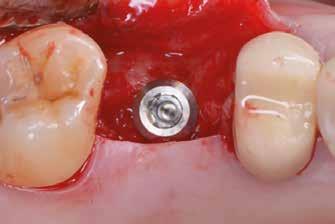

Sebészeti eljárás

Az eljárást helyi érzéstelenítés mellett végeztük (4%-os articaine-hidroklorid 1:100 000 adrenalinnal). Papillakímélő, U alakú palatális bemetszést végeztünk, teljes vastagságú nyálkahártyalebeny preparálás történt, a lebenyt bukkálisan feltekertük (5. ábra). A lebeny bukkálisan feltekert részén de-epitelizációt végeztük el, amellyel kompenzálni tudtuk a bukkális lágyszöveti defektust. Szakaszos előfúrást végeztünk, és a bredent copaSKY 4x10 implantátumot 30 Ncm behajtási nyomatékkal helyeztük be (6. ábra). Az implantátumot 1 mm-re szubkresztálisan helyeztük be, hogy később szélesebb emergenciaprofilt tudjunk kialakítani (7. ábra). Az egyedi ínyformázó úgy készült, hogy kompozitot vittünk fel a titánbázisra, és így formáztuk a lágyszöveteket a transzgingivális gyógyulási fázis során (8. ábra). Az egyéni ínyformázó tulipán formájú, hogy kialakítsa a kívánt emergenciaprofilt. A lágyszövetet feszülésmentesen zártuk #6/0 nem felszívódó, monofil fonallal (Optilene, B. Braun Deutschland; 9. a–b. ábra). Posztoperatív röntgenfelvétel készült, ami alapján az implantátum a szomszédos fogakkal párhuzamos elhelyezést mutatott (10. ábra). Posztoperatív utasításokat adtunk a páciensnek a műtéti terület körüli szájhigiénia fenntartása érdekében. A beavatkozást követő egy héttel a varratokat eltávolítottuk, és a kezelt terület kielégítő gyógyulást mutatott (11. ábra). A 4 hónap utáni késleltetett terhelést a páciens kívánsága szerint terveztük.

1. ábra: Műtét előtti fogászati panorámafelvétel, amelyen a hiányzó felső állcsont jobb első premolárisát és a szabad véggel rendelkező hidat láthatjuk. — 2. ábra: Az implantátum méreteinek megtervezése CBCT-vel. 3. ábra: Bukkális lágyrészdefektus. — 4. ábra: A biológiai szélesség értékelése a vertikális lágyszövetvastagság alapján. 5. ábra: Palatinális „tekercslebeny” – Palatal roll flap. — 6. ábra: Bredent medical copaSKY 4x10 implantátumbeültetés. 7. ábra: Szubkresztális implantátumbeültetés a várható biológiai szélességnek megfelelően.